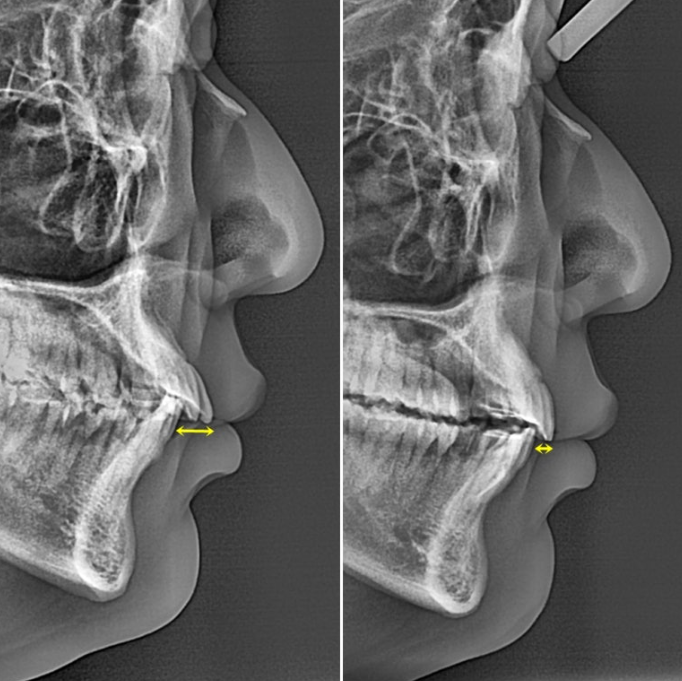

25.02~25.12

윗니 뻗침으로 인해 위 아래 간격이 크면 아랫입술이 그 사이로 숨습니다.

그래서 초진 아랫입술이 얇아보이는 거죠.

교정 후 위아래 간격이 줄면서 아랫입술이 제 모습을 드러냈습니다.

드라마틱한 돌출 해소는 포기한 간단한 인비절라인 라이트 교정이지만, 앞니 뻗침이라도 해결되니 미소가 한층 깔끔합니다.